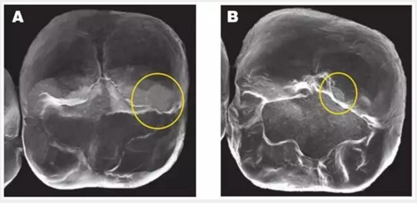

3. 對頜牙對牙冠的磨損:令人吃驚的是,各種類型的對頜牙(釉質(zhì)、鑄造金屬、復(fù)合樹脂還是瓷)都會對牙冠造成磨損平面。磨損程度最高的是瓷,其次是釉質(zhì)。鑄造金屬和復(fù)合樹脂也會造成磨損平面(見下圖)

圖像A顯示了對頜牙在BruxZir全鋯冠上造成的磨損的平面,黃色圓圈代表復(fù)合樹脂和釉質(zhì),橙色圓圈代表瓷。圖像B顯示了對頜牙為鑄造金屬修復(fù)體時,對切削類e.maxCAD單冠造成的磨損平面。兩種牙冠表面都有小的磨損平面,而且他們的對頜牙都顯示出了良好的結(jié)果。臨床上,對頜牙的每種材料(瓷、樹脂、釉質(zhì)、鑄造金屬)被磨損的程度幾乎是等同的。